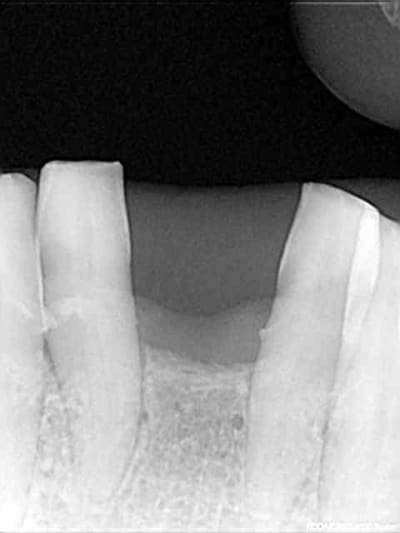

photo 1: début du cas

photo 2: fin d'intervention

photo 3: j+3mois

rx à j=0 et j+4 mois

ce qui est surprenant , c'est la présence d'os au niveau du col.